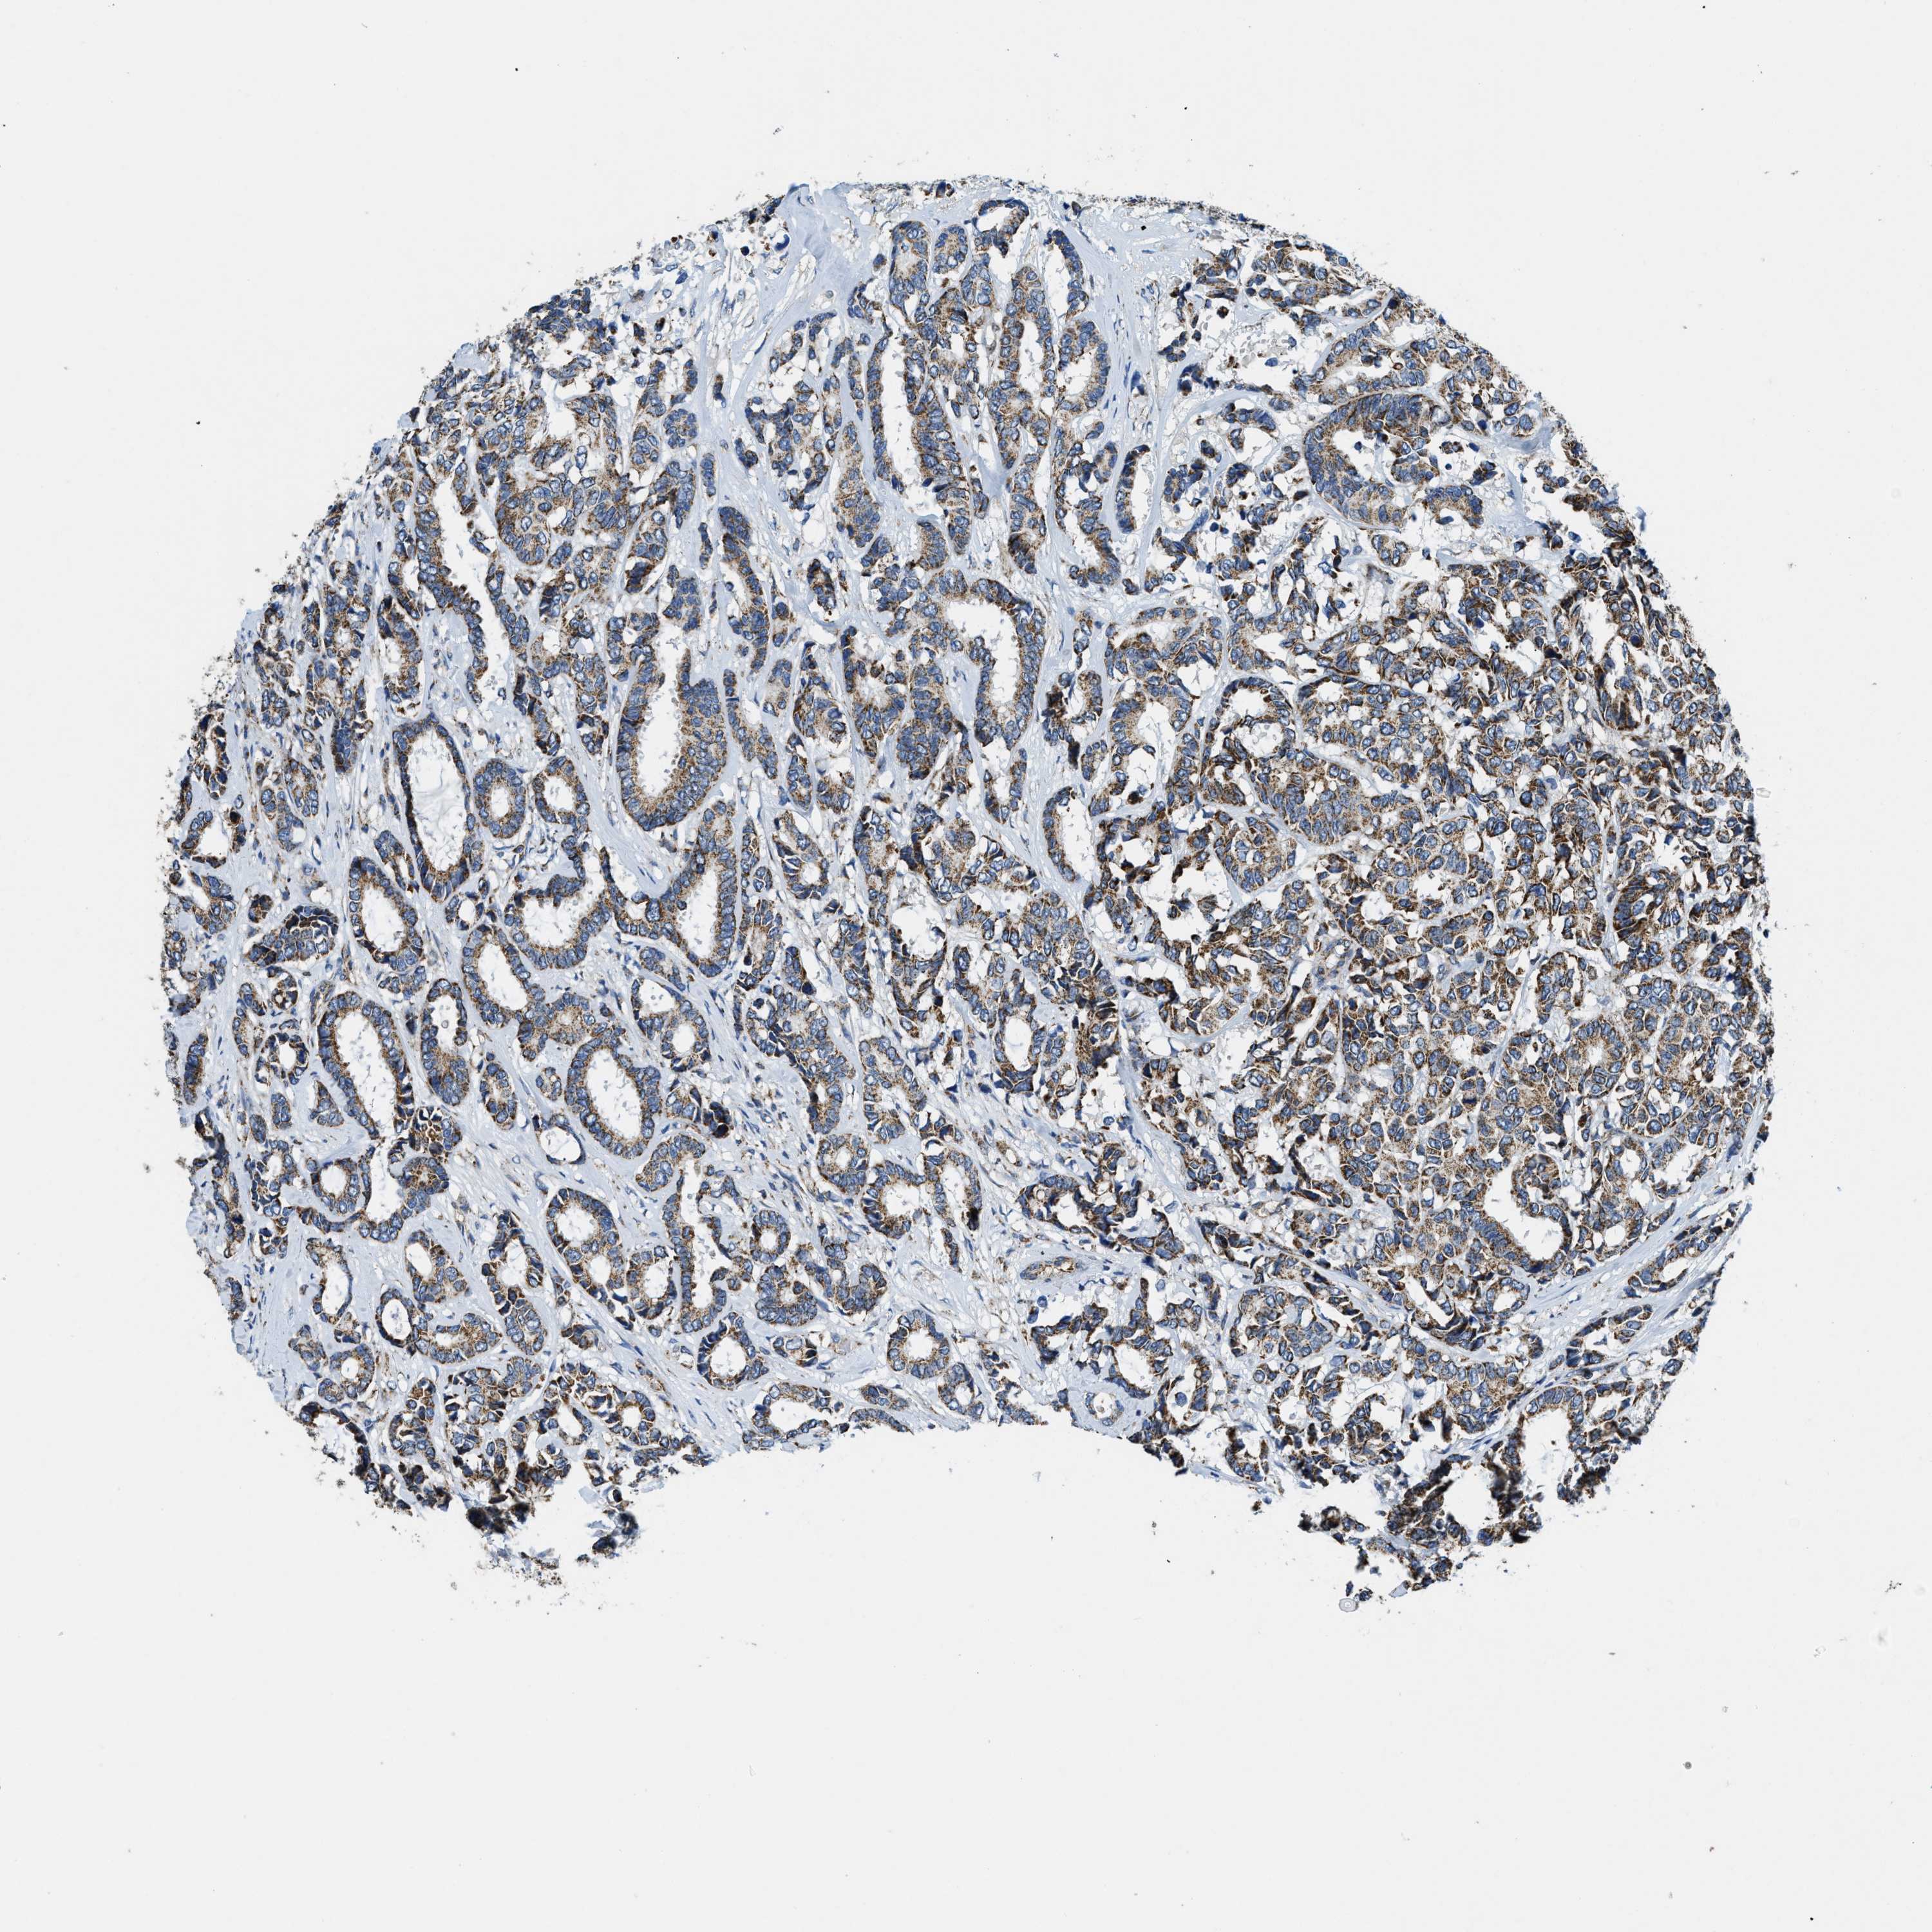

CANCER BREAST CANCER Show tissue menu

BRCA TCGA BRCA VALIDATION PROTEIN EXPRESSION